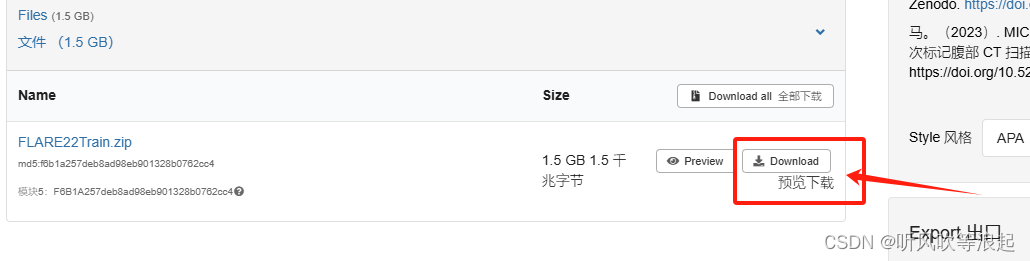

官方提供训练的数据集是:MICCAI FLARE22 挑战数据集,好像是腹部13类器官分割?

下载连接,也不是很大,就1.5 G多一点

数据集保存在:data/FLARE22Train/